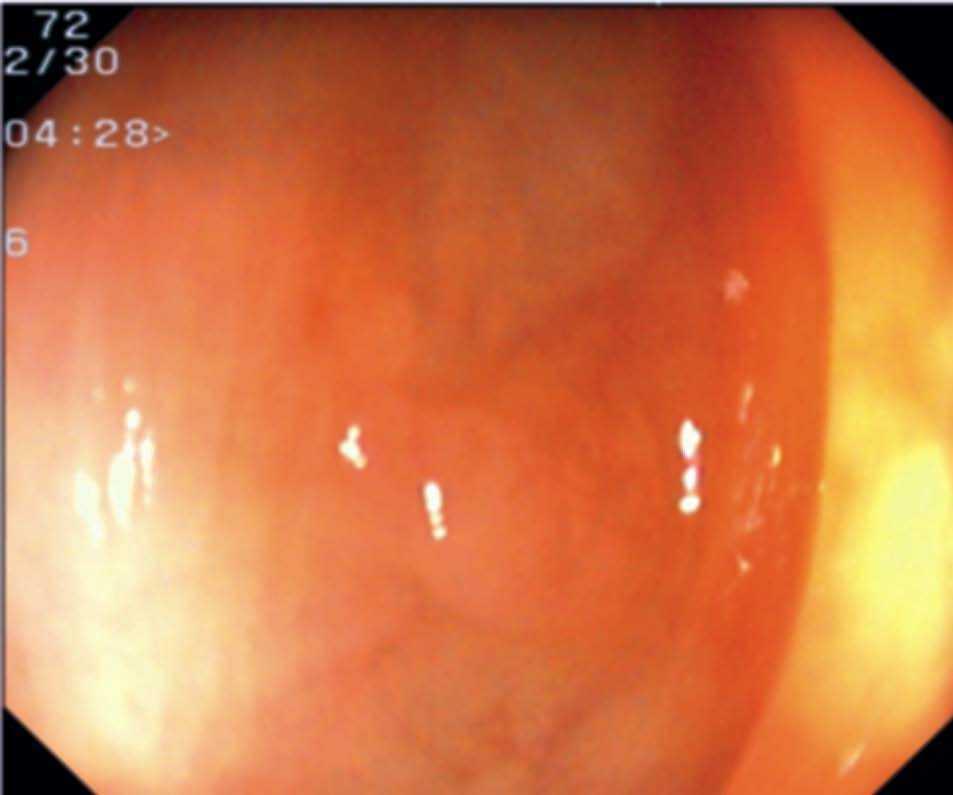

Fig. 3. Examples of flat lesions with conventional examination and after the application of indigo carmine 0.2-0.5%. a, b) Small flat adenoma, 3 mm in size. c, d) Large flat adenoma, 15 mm in size. e, f) Completely flat lesion (IIb in the Japanese classification). g, h) Depressed lesion, 3 mm in size) (IIc in the Japanese classification). I, J) Depressed lesion, 7 mm in size, histopathological study revealed submucosally invasive cancer (traditionally IIc in the Japanese classification, although recently such depressed lesions with a distinct central protrusion indicating submucosal invasion are termed IIc + Is). k, l) Flat elevated lesion with central depression, 10 mm in size, corresponding to a submucosally invasive cancer (IIa + IIc in the Japanese classification).